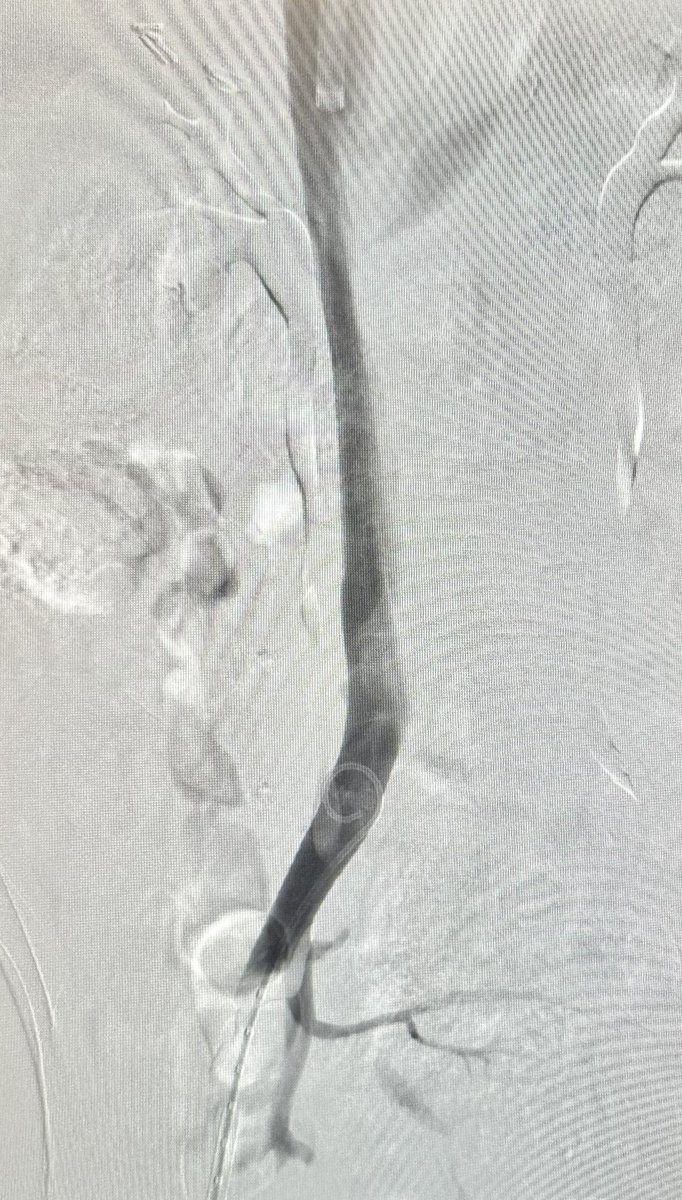

#PennsyInterventions CaseFiles: How would you approach this complex retrieval of angulated 10 yr old IVC filter with externalized embedded apex/hook and penetrating struts? Phila Angio Club Penn Cardiology Fellows Penn Cardiology Academy for CardioVascular Collaboration ReVascMed

2/ then we brought #CavaClear from Philips Healthcare to ablate embedded fibrotic tissue from hook and tip of filter to allow capture into the large 16 Fr sheath from Cook Medical